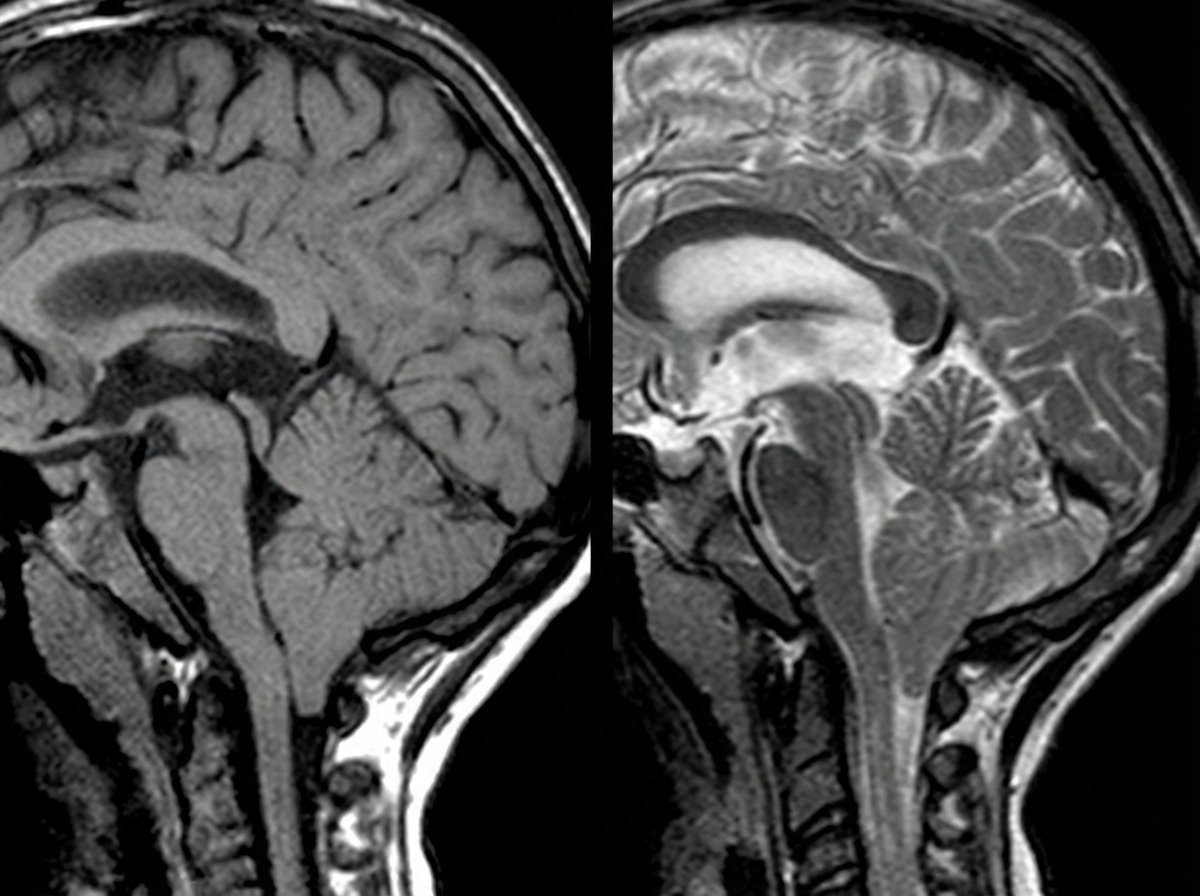

A 4-year-old boy is brought to the physician because of a progressive headache and neck pain for 2 weeks. During this period, he has had multiple episodes of dizziness and tingling sensations in his arms and hands. A year ago, he underwent closed reduction of a dislocated shoulder that he suffered after a fall. He underwent surgical removal of a sac-like protuberance on his lower back, soon after being born. His temperature is 36.7°C (98°F), pulse is 80/min, and blood pressure is 100/80 mm Hg. His neck is supple. Neurological examination shows sensorineural hearing loss bilaterally and normal gross motor function. Fundoscopy reveals bilateral optic disk swelling. An MRI of the brain is shown. Which of the following is the most likely cause of this patient's symptoms?